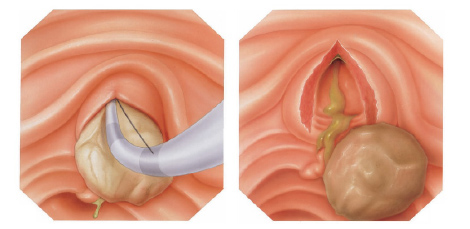

Mucosectomia é o procedimento realizado quando há necessidade de retirada de lesões maiores do trato gastrointestinal.

O exame de Mucosectomia é realizado através de injeção de liquido embaixo da lesão, através de uma agulha específica. Com isso a lesão se destaca das camadas mais profundas do intestino, diminuindo o risco de perfuração.

A retirada da lesão é feita com uma alça de polipectomia e o material é encaminhado para estudo anatomopatológico (no microscópio) da mesma forma que ocorre nas biópsias.

Geralmente apenas uma região do pólipo é que se apresenta de forma cancerosa. Se for realizada uma simples biópsia do pólipo, a região cancerosa pode não ser atingida e o diagnóstico de câncer não ser realizado. Para se ter certeza do diagnóstico, o pólipo inteiro deve ser removido através do procedimento chamado de polipectomia.

O que é a polipectomia?

A polipectomia é a remoção completa de um pólipo permitindo assim o diagnóstico exato e muitas vezes a cura do próprio problema. Existem várias técnicas para a realização do procedimento que dependem do tamanho e do tipo de pólipo a ser ressecado.

Polipectomia com pinça

Pequenos pólipos podem ser removidos com segurança usando-se apenas uma pinça.

Polipectomia com alça diatérmica

Pólipos maiores necessitam ser removidos com alça e corrente de cauterização. Este procedimento permite cortar a base do pólipo e ao mesmo tempo coagular o local para evitar sangramentos.

Porém alguns pólipos possuem a base (pedículo) largo onde passam vasos calibrosos e por isto tem risco aumentado de sangramento na retirada mesmo usando a corrente de coagulação.

Nestes casos algumas medidas podem ser realizadas para diminuir o risco de sangramento:

Injeção de adrenalina na base do pólipo

Colocação de um laço na base do pólipo para estrangular o pedículo

Alguns pólipos são tão grandes que não podem ser removidos inteiros. Nestes casos o pólipo é retirado em pedaços para poder garantir a sua remoção completa.

Alguns pólipos não possuem a base alongada (pedículo), estes são chamados de pólipos sésseis. A remoção destes pólipos possui risco maior de perfuração do órgão pois como são planos ficam muito próximos da parede externa do órgão.

Mucosectomia

Para diminuir este risco, injeta-se com um uma agulha uma solução abaixo do pólipo para que ele levante e fique mais longe da parede do órgão. Após isto passa-se a alça diatérmica e realiza-se o

procedimento de polipectomia.